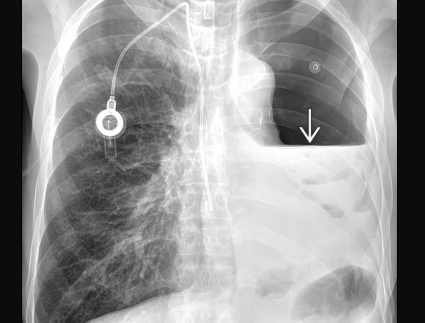

Migration caudale de l’air

Empyème compliqué d’une fistule parenchymo-pleurale